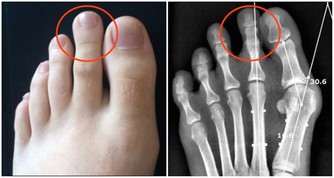

一、常年手腳冰涼的原因缺鐵研究表明,常年手腳冰涼的人,血液中鐵元素含量不足。

當人體缺鐵時,由於血紅素較少而影響了血液的攜氧能力,造成組織能量代謝發生障礙。並且血液流通不順暢,產生熱量不足就會導致手腳冰涼。